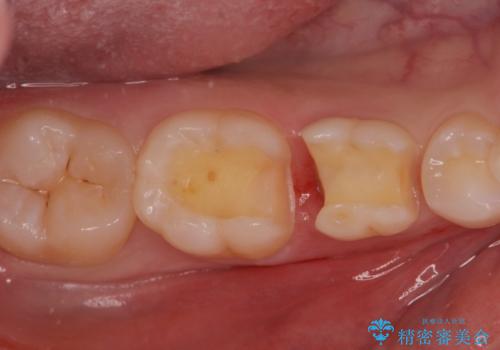

歯が染みる。セラミックインレー治療。

- 歯が染みるとの事で来院。

レントゲンを撮影したところ虫歯がありましたので拡大鏡下で虫歯を取り除いた後、e-maxインレーにて治療を行いました。

手前の歯は乳歯でしたが、患者様と相談しなるべく長持ちさせたいとの事でしたのでe-maxインレーでの治療となりました。

適合の良い詰め物が入りました。